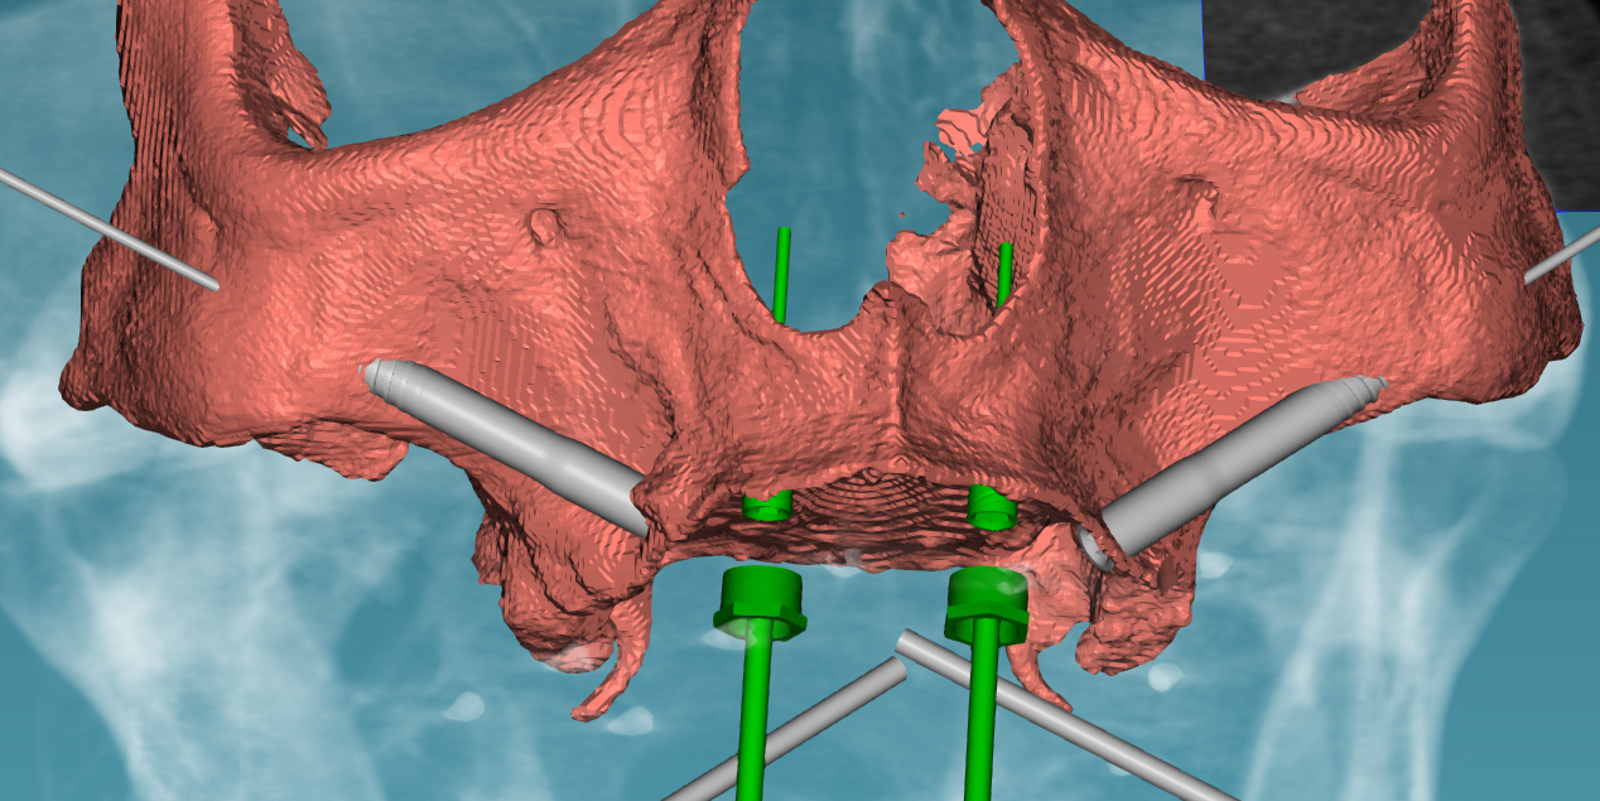

Digitale planning

Het toepassen van digitale planning is van groot belang bij implantaten met remote verankering, omdat dit zorgt voor maximale voorspelbaarheid. Door CBCT-data, intraorale scans en virtuele implantaatpositionering te combineren, kunnen de optimale locatie, angulatie en diepte vooraf worden bepaald, rekening houdend met botvolume en aanwezige anatomische structuren (figuur 3). Dit verlaagt het risico op misplaatsing, verhoogt de stabiliteit en draagt bij aan efficiëntere behandelingen met minder complicaties en correcties achteraf.

Een voorbeeld met digitale planning voor een quad zygoma-rehabilitatie.

Gezien het extreem beperkte botvolume werd gekozen voor een vaste maxillaire rehabilitatie met een zygomatisch implantaatconcept, waarbij augmentatieve reconstructies werden vermeden. Met behulp van digitale planning in JDreal-software werden twee zygoma-implantaten en twee nasale/anterior-implantaten virtueel gepositioneerd (figuur 12). Op basis van deze planning werd een 3D metaal geprinte boormal ontworpen om een nauwkeurige, begeleide plaatsing volgens het geplande traject te kunnen garanderen.

Digitale planning van de implantaten (twee zygoma’s en twee nasale).